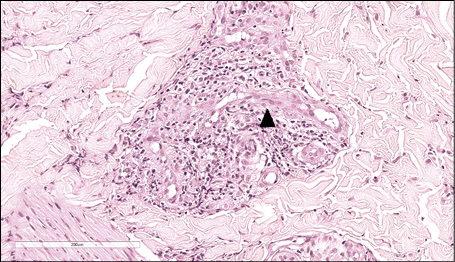

At scanning magnification, the histopathology showed a broad dermo-epidermal ulceration with an underlying purulent base (Figure 2). At higher magnification, the epidermis was characterized by necrotic keratinocytes with pycnotic nuclei and dense eosinophilic cytoplasm (Figure 3, arrowhead) and by scattered keratinocytes with a “shadow cell” appearance (enlarged cells with eosinophilic cytoplasm without well-defined nuclei [Figure 3, arrow]); suppurative changes were detected within the papillary dermis with marked neutrophilic exocytosis (Figure 3, asterisk). Some keratinocytes showed ballooning degeneration (Figure 4, arrow). An interstitial and perivascular/peri-adnexal inflammatory infiltrate composed of neutrophils and lymphocytes was observed in the deep dermis, associated with endothelial swelling (Figure 5, arrowhead) without fibrinoid necrosis of the vascular wall.

Figure 5 - Haematoxylin and eosin (H&E) stain. An interstitial and perivascular/peri-adnexal inflammatory infiltrate composed of neutrophils and lymphocytes was observed in the deep dermis, associated with endothelial swelling (arrowhead) without fibrinoid necrosis of the vascular wall (magnification 40x).